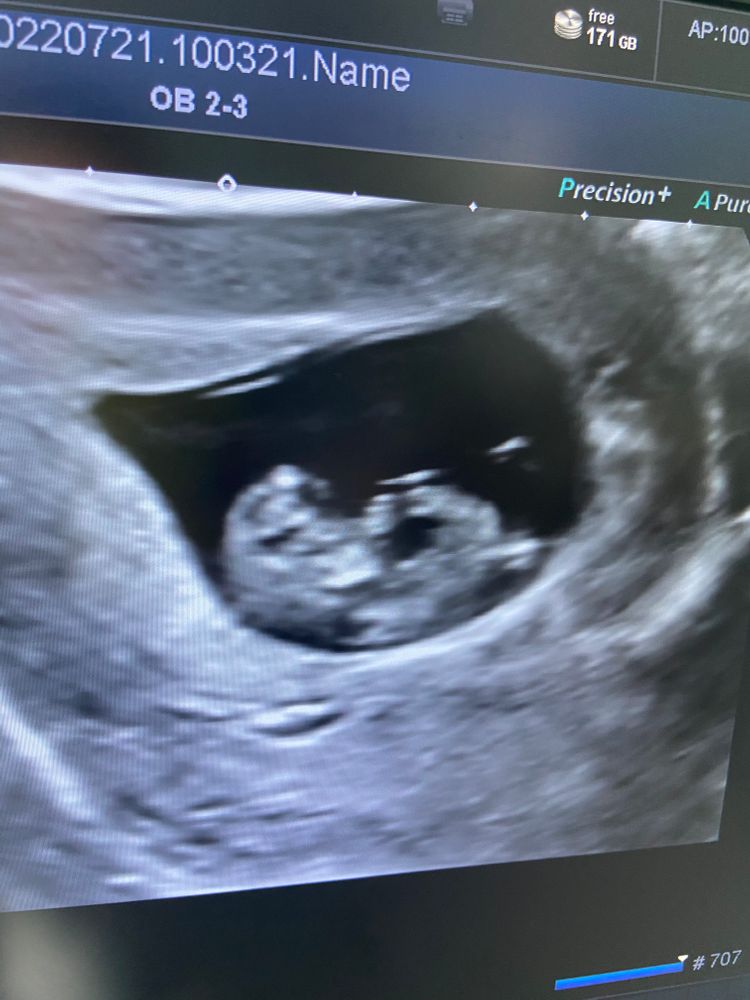

Мария Ткач в ЭКО-мама 3 года 10 недель )растём❤️ РАЗНОЕ (если тема больше не подходит ни к одной категории, пишем сюда) Посмотрите еще 20 записей на эту тему Отменить Ответить Ирина Большой какой, растите дальше 21.07.2022 Ответить Tetra Какие большие уже 😍 Растите 🤞🏻💫 21.07.2022 Ответить Anna As Какое счастье 😍😍😘😘 21.07.2022 Ответить Ирина Люблю такие фотографии, в них столько смысла, столько любви, столько жизни💕 21.07.2022 Ответить Lena Какой мимимишный❤️ 21.07.2022 Ответить Йога и бассейн после какого дпп? Забанить человека Чаты Беременных Выберите чат: Январята-2026 Февралята-2026 Мартята-2026 Апрелята-2026 Майчата-2026 Июнята-2026 Июлята-2026 Августята-2026